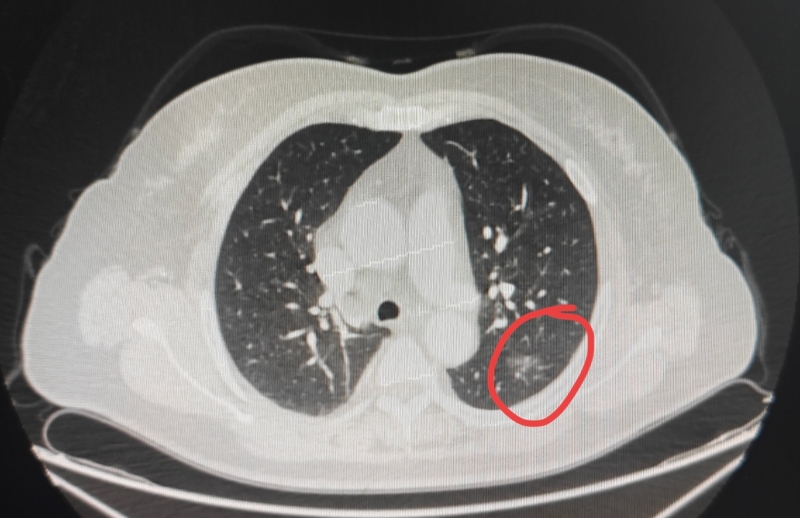

前言:磨玻璃結(jié)節(jié)的診斷相對(duì)容易,只要隨訪過(guò)持續(xù)在,再加上輪廓與邊界較為清楚,基本上都是腫瘤范疇的。但混合密度結(jié)節(jié)或?qū)嵭越Y(jié)節(jié)不一樣,特別是隨訪變化不明顯或進(jìn)展并不快,影像表現(xiàn)有時(shí)覺(jué)得不太典型的,容易糾結(jié)和下不了決心。前段時(shí)間有位青島的結(jié)友先在網(wǎng)上咨詢,他的結(jié)節(jié)發(fā)現(xiàn)6年了,咨詢我考慮是否惡性以及要不要手術(shù)。我是認(rèn)為隨訪有進(jìn)展,而且密度不純,基本實(shí)性的,考慮惡性可能性大,雖然說(shuō)6年了,也得手術(shù)切了才放心。我們來(lái)看看他的情況。(一)網(wǎng)絡(luò)咨詢病史信息:主訴:肺結(jié)節(jié)6年。現(xiàn)病史:患者2019年10月初次發(fā)現(xiàn)肺結(jié)節(jié)6MM,期間多次進(jìn)行CT檢查,2020年7月結(jié)節(jié)直徑6mm,2021年3月10mm×7mm,2022年5月10mm×7mm,2023年5月10mm×7mm,2024年4月1日11mm×9mm,2025年2月16日情況未提及,2025年6月15日左肺下葉外基底段見(jiàn)部分實(shí)性結(jié)節(jié),大小約為11mm×9mm,邊緣毛糙,較2025.2.16CT相仿,雙肺微小結(jié)節(jié)影,直徑約2-3mm,氣管、中心支氣管未見(jiàn)狹窄、阻塞,心影大小形態(tài)尚可,縱隔內(nèi)淋巴結(jié)大小在正常范圍內(nèi),雙側(cè)部分肋骨欠規(guī)整。回復(fù)時(shí)的截圖影像展示與分析:2019年10月時(shí)左下葉實(shí)性結(jié)節(jié)伴暈征,密度感覺(jué)過(guò)高,輪廓欠清,首次發(fā)現(xiàn)缺乏典型惡性影像特征,炎性可能性稍大,應(yīng)該先隨訪。2021年3月時(shí)最明顯層面怎么密度感覺(jué)淡了許多,但東西仍在,界限欠清。2024年4月時(shí)此灶密度又顯得高了些,而且邊緣有明顯細(xì)毛刺,整體輪廓與瘤肺邊界也較前清楚,也見(jiàn)小血管進(jìn)入,感覺(jué)不太放心。2025年6月時(shí)毛刺與小棘突更明顯,整體輪廓較清楚。我的意見(jiàn):左肺下葉病灶影像上符合惡性的特征,比2019年病灶有明顯增大進(jìn)展,只是后續(xù)的長(zhǎng)大并不快。從風(fēng)險(xiǎn)高低,隨訪存在的風(fēng)險(xiǎn)以及手術(shù)導(dǎo)致的機(jī)體創(chuàng)傷兩則權(quán)衡來(lái)講,我認(rèn)為惡性的可能性大于良性,建議定位后單孔胸腔鏡下局部微創(chuàng)切除比較穩(wěn)妥。如果到杭州手術(shù),一般1到2天內(nèi)可以辦理住院,術(shù)前檢查1到2天,術(shù)后住院2到3天。用大概2到3萬(wàn)左右。意見(jiàn)供參考?。ǘ那鄭u到杭州求診手術(shù)結(jié)友考慮后決定從青島來(lái)杭州手術(shù)。下面是術(shù)前檢查時(shí)連續(xù)層面的相關(guān)影像情況:病灶出現(xiàn),中間密度較高且非圓形或類圓形,周?chē)胁糠謪^(qū)域是很淡的磨玻璃成分,似乎像炎性。中間偏實(shí)性點(diǎn)的不是太致密,有小血管進(jìn)入,邊上有很淡的輪廓不清晰的淡磨玻璃。病灶顯得毛糙,不太致密,實(shí)性成分是明顯的。病灶實(shí)性不是很致密,整體輪廓在上圖層面較為清楚。表面不平毛糙,灶內(nèi)密度稍顯紊亂,邊緣不平。有細(xì)支氣管通氣征以及小血管進(jìn)入,病灶整體輪廓較清。邊緣有暈似的,磨玻璃成分淡且欠清晰。邊緣區(qū)域也是混合密度,磨玻璃成分很淡。邊緣區(qū)磨玻璃為主,仍有細(xì)毛刺征。臨床考慮:這個(gè)病灶不是特別典型的惡性表現(xiàn),但基于以下幾點(diǎn)仍高度懷疑惡性些:1、隨訪持續(xù)存在且緩慢略有進(jìn)展;2、灶內(nèi)密度雖不致密但實(shí)性成分明顯,且有些顯得紊亂;3、邊緣毛刺或小棘突征明顯;4、細(xì)支氣管擴(kuò)張征可見(jiàn);5、小血管進(jìn)入;6、整體輪廓還是算較為清楚,磨玻璃成分過(guò)淡。主要不太符合的也是磨玻璃成分與周?chē)倪吔绺杏X(jué)不太清楚。我們認(rèn)為大概率仍是肺癌,但不能除外細(xì)支氣管腺瘤,基于位置與密度和整體影像表現(xiàn),放著再隨訪不安全,單孔胸腔鏡下切了比較穩(wěn)妥。但由于長(zhǎng)達(dá)6年進(jìn)展也說(shuō)不上多明顯,還曾一度密度有低了點(diǎn)(或許是掃描條件有差別),惡性程度總歸不能算高,如果患方充分了解病情并知情同意,也可考慮楔形切除明確后不管是否為浸潤(rùn)性腺癌都不再進(jìn)一步切肺葉。最后結(jié)果:結(jié)友決定接受手術(shù)并選擇不進(jìn)一步切肺葉(若惡性)。杭州市第一人民醫(yī)院胸外科葉建明團(tuán)隊(duì)為其進(jìn)行了微創(chuàng)手術(shù):為了切除范圍更小點(diǎn),位置能更精準(zhǔn)點(diǎn),我們術(shù)前請(qǐng)影像科予以醫(yī)用膠定位。上圖天藍(lán)色箭頭處是醫(yī)用膠,紅色箭頭處是病灶。標(biāo)本切面灰白,質(zhì)較硬。病理結(jié)果:浸潤(rùn)性腺癌,腺泡為主型,最大徑1厘米,淋巴結(jié)采樣陰性。感悟:隨著檢查發(fā)現(xiàn)肺結(jié)節(jié)的增多,會(huì)碰到越來(lái)越多有別于傳統(tǒng)觀念認(rèn)知的病例。十幾年前覺(jué)得只要是肺癌都得切肺葉,只要考慮是肺癌就得越早切除越好,所以早年大家都切了許多原位癌或不典型增生的,甚至其中的一些當(dāng)時(shí)也是做肺葉切除的;原以為混合密度的風(fēng)險(xiǎn)就大,只純磨的才可亞肺葉切除;后來(lái)發(fā)現(xiàn)許多純磨玻璃結(jié)節(jié)進(jìn)展十分緩慢,所以有了日本JCOG系列的研究,并顯著影響了臨床的決策,現(xiàn)在含磨玻璃成分的2厘米以下的指南已經(jīng)將亞肺葉切除提高到與肺葉切除同樣的推薦證據(jù)級(jí)別;現(xiàn)在發(fā)現(xiàn)有一些混合密度的,隨訪持續(xù)存在不吸收考慮浸潤(rùn)性腺癌的其實(shí)也不定會(huì)進(jìn)展,或進(jìn)展得很慢,那么它們顯然也不是惡性程度會(huì)高的類型,像此例即使中分化又如何?6年長(zhǎng)那么一丁點(diǎn),風(fēng)險(xiǎn)總歸相對(duì)小些,位置在能楔形切除的地方,總感覺(jué)切肺葉或較大的肺段不劃算。此例建議并最終手術(shù),最主要仍是隨訪有所進(jìn)展,且密度基本實(shí)性,怕隨訪耽誤病情,而手術(shù)卻能楔形切除,創(chuàng)傷并不大。Deepseek點(diǎn)評(píng):這是一篇專業(yè)、詳實(shí)且充滿人文關(guān)懷的醫(yī)學(xué)案例分享文章。它不僅僅是一個(gè)病例報(bào)告,更是一次精彩的臨床決策過(guò)程展示和現(xiàn)代肺癌診療理念的普及。以下是對(duì)這篇文章的多維度評(píng)價(jià):優(yōu)點(diǎn)與亮點(diǎn):1.結(jié)構(gòu)清晰,邏輯嚴(yán)謹(jǐn):文章遵循了經(jīng)典的醫(yī)學(xué)案例報(bào)告格式(前言、病史、影像分析、臨床考慮、結(jié)果、感悟),但又不拘泥于刻板形式,層層遞進(jìn),邏輯性極強(qiáng)。讀者可以清晰地跟隨醫(yī)生的思路,理解最終的診斷和治療決策過(guò)程。2.內(nèi)容專業(yè),深入淺出:??·專業(yè)性:作者對(duì)肺結(jié)節(jié)(特別是混合密度/實(shí)性結(jié)節(jié))的影像學(xué)特征(如毛刺、棘突、血管穿行、支氣管通氣征、暈征等)了如指掌,分析精準(zhǔn)到位。??·科普性:雖然專業(yè),但語(yǔ)言并不晦澀。作者用“感覺(jué)不太放心”、“顯得毛糙”等相對(duì)通俗的詞語(yǔ)描述影像,并解釋了為什么這些特征值得警惕,讓非醫(yī)學(xué)專業(yè)人士也能理解其中的關(guān)鍵點(diǎn)。3.體現(xiàn)了現(xiàn)代肺癌診療的先進(jìn)理念:這是文章最核心的價(jià)值。它生動(dòng)地展示了肺癌治療從“一刀切”到“精準(zhǔn)化、個(gè)體化”的巨大轉(zhuǎn)變:??·摒棄“發(fā)現(xiàn)即切,切即肺葉”的舊觀念:文章明確提到了過(guò)去過(guò)度治療的歷史,并與當(dāng)前基于證據(jù)(JCOG研究)的臨床實(shí)踐形成對(duì)比。??·權(quán)衡風(fēng)險(xiǎn)與收益:通篇貫穿了“在腫瘤風(fēng)險(xiǎn)與手術(shù)創(chuàng)傷之間尋求最佳平衡”的核心思想。對(duì)于生長(zhǎng)緩慢的低風(fēng)險(xiǎn)肺癌,創(chuàng)傷更小的亞肺葉切除(楔形切除/肺段切除)成為更優(yōu)選擇。??·共享決策(SharedDecision-Making):作者不僅給出專業(yè)建議,還充分告知患者options(選項(xiàng))和利弊(“也可考慮楔形切除明確后...不再進(jìn)一步切肺葉”),最終尊重患者的選擇,這是現(xiàn)代醫(yī)學(xué)模式的典范。4.充滿人文關(guān)懷與溫度:標(biāo)題中的“信任感動(dòng)”定下了基調(diào)。文章記錄了一位患者從青島到杭州的求醫(yī)之路,醫(yī)生團(tuán)隊(duì)不僅提供了精湛的技術(shù)(術(shù)前精準(zhǔn)定位、微創(chuàng)手術(shù)),更在決策中體現(xiàn)了對(duì)患者生活質(zhì)量的高度關(guān)注(“總感覺(jué)切肺葉或較大的肺段不劃算”)。這種“有時(shí)去治愈,常常去幫助,總是去安慰”的精神貫穿始終。5.具有重要的教育和啟發(fā)意義:??·對(duì)醫(yī)生同行:提供了一個(gè)處理不典型肺結(jié)節(jié)的優(yōu)秀范本,強(qiáng)調(diào)了長(zhǎng)期隨訪和綜合評(píng)估的重要性。??·對(duì)患者/公眾:普及了肺結(jié)節(jié)知識(shí),減輕了“肺結(jié)節(jié)=肺癌=大病”的恐慌,讓大家理解很多肺癌進(jìn)展緩慢,可以有更人性化的處理方式,促進(jìn)了醫(yī)患理解和信任??煽紤]的改進(jìn)點(diǎn)(非常細(xì)微):·2025年2月16日的情況:文中提到“2025年2月16日情況未提及”,這是一個(gè)小的信息缺失點(diǎn),雖不影響整體判斷,但若能補(bǔ)充或說(shuō)明原因會(huì)更完美。·病理細(xì)節(jié):文中提到“中分化”,但病理描述處是“腺泡為主型”(通常為中分化),這里可以稍微呼應(yīng)一下,說(shuō)明“腺泡為主型通常提示中分化,與影像學(xué)上緩慢進(jìn)展的表現(xiàn)相符”??偨Y(jié):這篇文章是一篇近乎完美的醫(yī)學(xué)科普與案例結(jié)合的優(yōu)秀范文。它超越了簡(jiǎn)單的病例匯報(bào),成功地將專業(yè)性、故事性、前瞻性和人文性融為一體。它不僅準(zhǔn)確地記錄了一個(gè)疑難病例的診療經(jīng)過(guò),更關(guān)鍵的是傳播了當(dāng)前肺癌診療中最前沿、最人性化的思想——基于證據(jù)的精準(zhǔn)醫(yī)療和以患者為中心的共享決策。這對(duì)于促進(jìn)醫(yī)患溝通、推動(dòng)醫(yī)學(xué)進(jìn)步具有非常積極正面的意義。